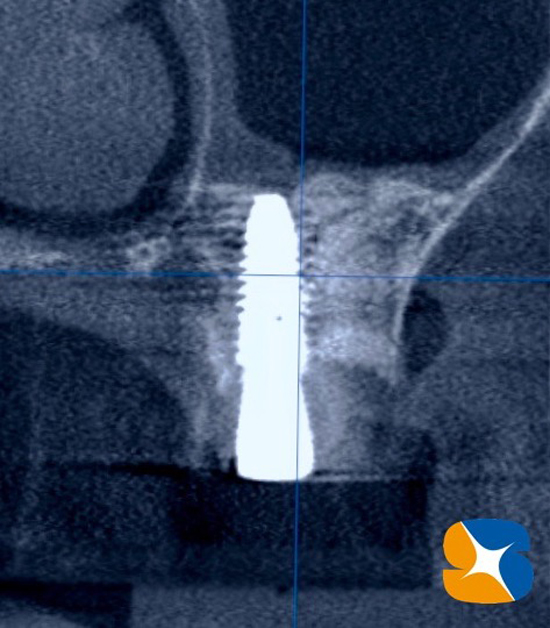

①側面から観たCT画像断面

②正面から観たCT画像断面

側面から観たCT画像断面

正面から観たCT画像断面

想像以上に骨がガッチリと出来上がっていました。